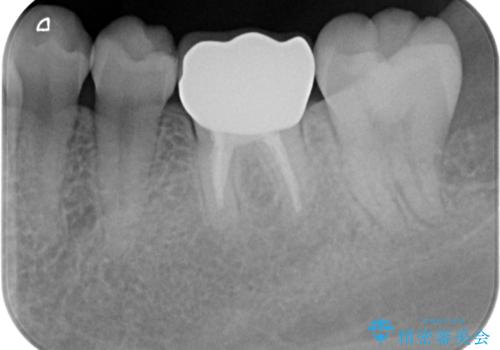

- 他院で根管治療を終えて被せ物を入れたいとの事で来院。

形を整えて型取りをし、ジルコニアクラウンを装着しました。

被せ物が入りました。

根管治療が終わった歯は被せ物を装着しないと細菌が根管内に侵入し根の再発のリスクが増えるため早急に被せ物を入れる事をお勧めします。